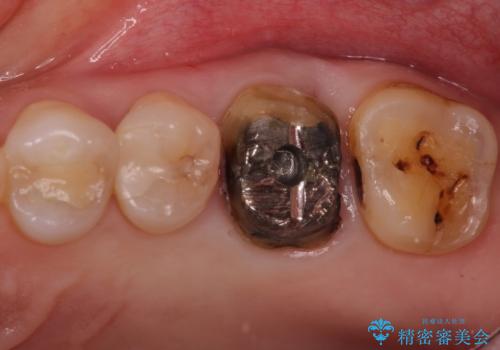

- 検査の結果被せ物の下に虫歯が確認された患者様です。

虫歯を取りきった後セラミッククラウンでの修復処置を行います。

被せ物の裏側の虫歯は被せ物を取らないと除去できません。

今回は過去に治療された部分をすべてやり直しました。